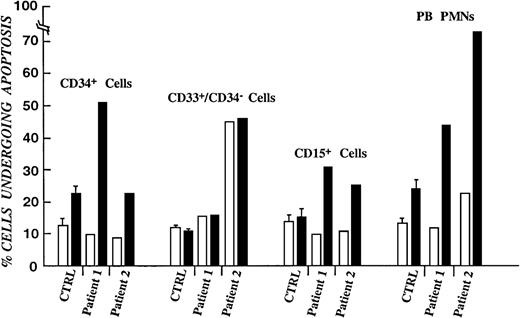

To confirm the hypothesis that impaired survival of myeloid progenitors contributes to the neutropenic phenotype of myelokathexis, annexin-V–FITC–propidium iodide staining of bone marrow hematopoietic subpopulations and flow cytometry analysis was performed.40This method permits evaluation of cells in the early and late stages of apoptosis. The rate of apoptotic cell death was studied in freshly isolated cells and after storage overnight at 37°C. As shown in Figure 2, the rate of apoptotic cell death in freshly isolated cells did not differ significantly from control populations. However, overnight storage of myelokathexis cells at 37°C resulted in apoptosis of approximately 25% to 50% of CD34+ cells, up to 50% of CD33+/CD34− cells, and >30% of CD15+/CD34−/CD33− cells compared with 20%, 7%, and 10% apoptosis in respective cell populations from healthy volunteers. Peripheral blood neutrophils were also analyzed and revealed up to 70% cells undergoing spontaneous apoptosis on overnight storage compared with 25% in control (Figure2). These data demonstrate that the insufficient supply of neutrophils to the peripheral blood in myelokathexis is caused, at least in part, by accelerated apoptosis of bone marrow progenitor cells.

Percentage of purified bone marrow progenitor cells undergoing apoptotic cell death.

From healthy volunteers and patients with myelokathexis, as determined by FACS analysis of annexin-V–fluorescein isothiocyanate–propidium iodide–labeled cells. (open bars) Freshly isolated cells. (filled bars) Same cell populations stored overnight in 10% autologous serum. Data for control subpopulations represent mean value of 4 healthy volunteers ± SD.

Percentage of purified bone marrow progenitor cells undergoing apoptotic cell death.

From healthy volunteers and patients with myelokathexis, as determined by FACS analysis of annexin-V–fluorescein isothiocyanate–propidium iodide–labeled cells. (open bars) Freshly isolated cells. (filled bars) Same cell populations stored overnight in 10% autologous serum. Data for control subpopulations represent mean value of 4 healthy volunteers ± SD.

To delineate further the cell populations affected in myelokathexis, apoptosis studies were conducted with bone marrow-derived CD34+, CD33+/CD34−, and CD15+/CD34−/CD33− cell populations. These studies demonstrated that the rate of spontaneous apoptotic cell death was accelerated in bone marrow-derived myeloid progenitor cells from these patients (Figure 2). Analysis of bone marrow CD34+ cells by colony-forming assay demonstrated a substantial reduction in the bone marrow pool of myeloid-committed progenitors in patients with myelokathexis (Figure 3). Taken together, these data indicate that accelerated apoptosis of myeloid-committed progenitor cells contributes to the marked reduction in delivery of neutrophils from the bone marrow to the peripheral blood in myelokathexis.